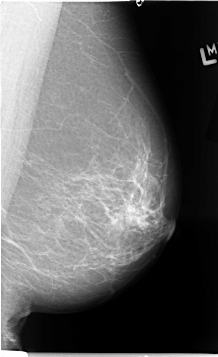

B_3068_1.RIGHT_CC

LEFT_CC LINES 4648 PIXELS_PER_LINE 2688 BITS_PER_PIXEL 12 RESOLUTION 50 NON_OVERLAY

FILE: B_3068_1.RIGHT_CC.OVERLAY

TOTAL_ABNORMALITIES 1

ABNORMALITY 1

LESION_TYPE MASS SHAPE LOBULATED MARGINS CIRCUMSCRIBED-ILL_DEFINED

ASSESSMENT 4

SUBTLETY 4

PATHOLOGY MALIGNANT

TOTAL_OUTLINES 1

BOUNDARY